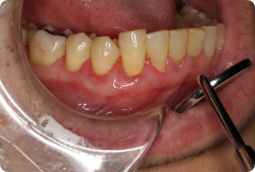

BEFORE

症例概要

年代、性別

40代、男性

主訴

歯茎が下がってきた

診断

下顎左側犬歯、小臼歯の歯肉退縮

治療内容

歯周基本治療(ブラッシング指導)、歯軋り用マウスピースの装着、結合組織移植術(CTG)

治療期間

2ヶ月程度

治療リスク

術後の一時的な痛み、歯肉の退縮量や厚さによっては再度手術が必要

治療費用

165,000円(税込)